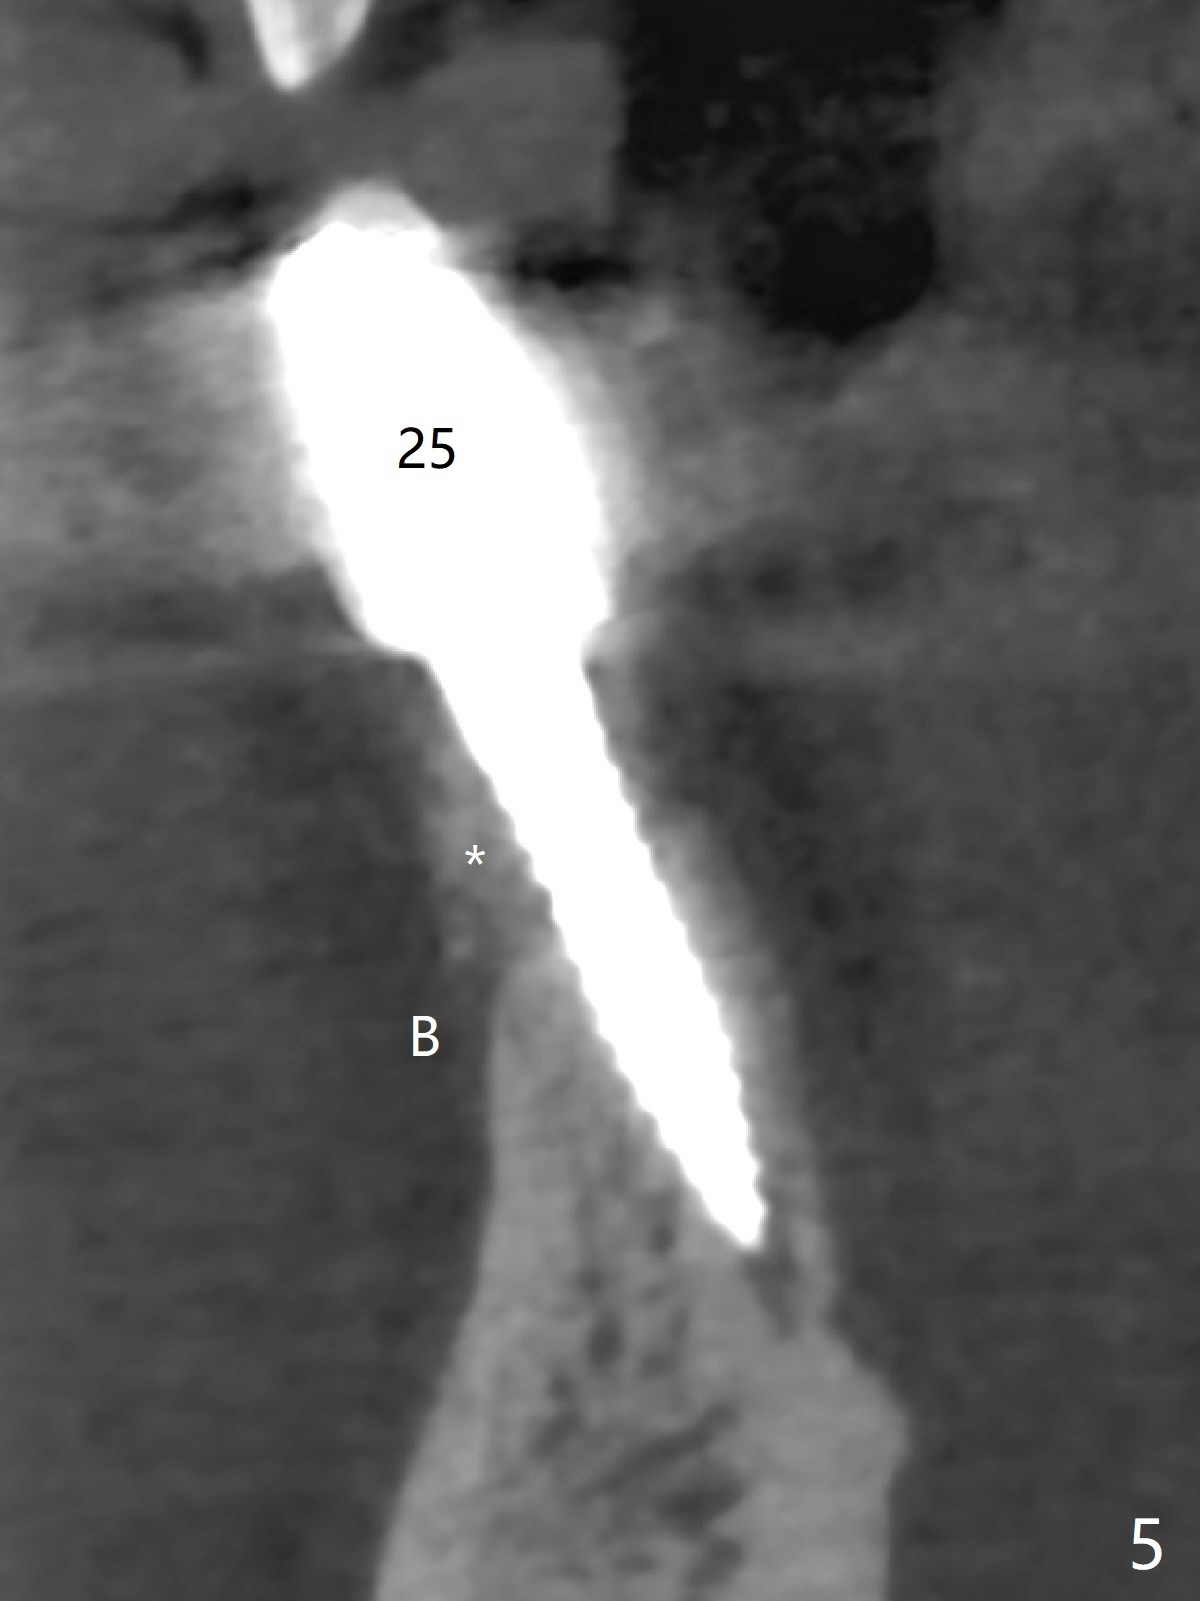

The fenetration found buccal to #25 two months post cementation persists, although asymptomatic, 4 months post cementation. Blood is drawn for PRF. In fact the implants at #24 and 25 are exposed buccal; there is limited amount of the buccal bone (Fig.1 *). After granulation tissue removal, Titanium brush is used to clean the implant threads. Allograft and Osteogen are mixed with PRF liquid to form gel, which is placed over the exposed implant threads. The bone graft is covered with a piece of PRF membrane and a piece of collagen membrane (Fig.2 C). Immediately postop PA (Fig.3) and CBCT (Fig.4) show that the implants have sufficient clearance between them. The implant thread exposure is most likely due to failure to place the implants deep enough and the implants are slightly large relative to the ridge (Fig.5-8). If the bone graft does not heal, new type of 1-piece implants (Fig.9,10 (green) smaller in diameter, 2 or 2.5 mm ) with longer abutment (pink) will be placed subcrestal buccal with guide.